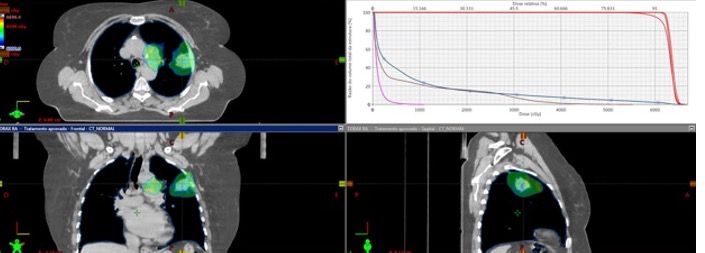

After multidisciplinary team consultation, the patient received radiotherapy (Figure 4) with concurrent weekly paclitaxel and carboplatin. The treatment was well tolerated, and the patient had no toxicity. A CT scan after therapy showed a good response (Figure 5). After chemo-radiotherapy treatment, the patient started durvalumab as consolidation therapy.

Figure 4. Radiotherapy plan.